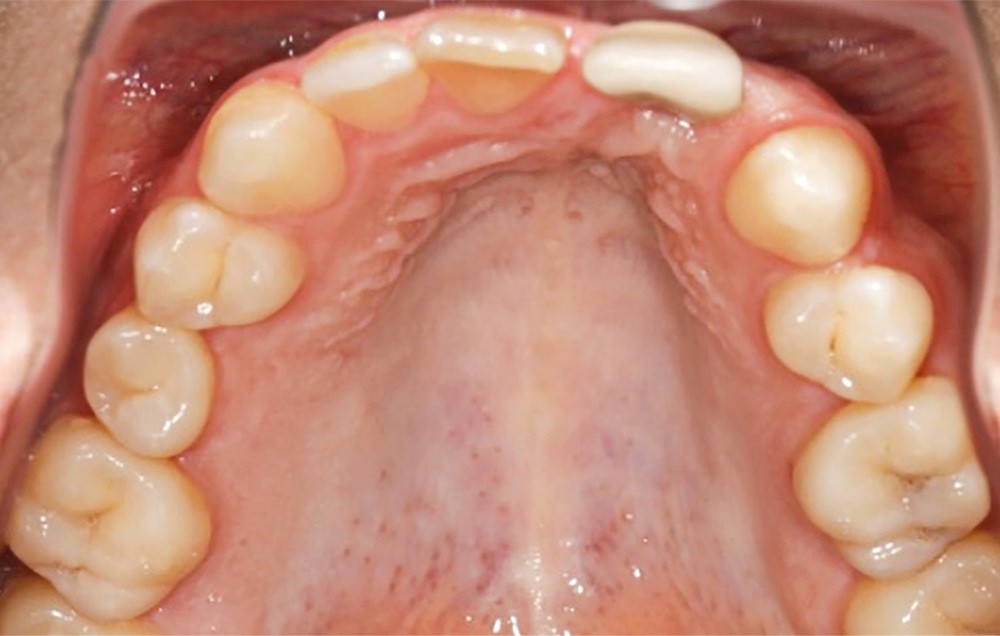

- au niveau dentaire : une arcade maxillaire asymétrique avec déviation du milieu maxillaire à gauche. On note l’absence de 21, 22, 25, 35 et 45, une classe II droite et gauche avec infraclusion antérieure et la présence d’un implant en place de 21 avec un diastème de 3 mm entre 21 et 23 (fig. 3) ;